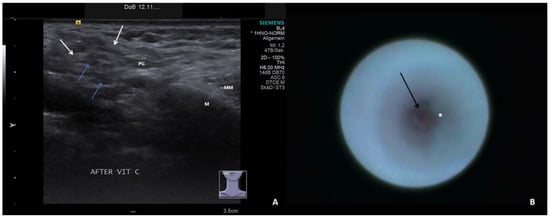

- Sialodochitis with a tendency toward duct narrowing (SD + Sten: SD and thickness of the duct wall with a tendency toward luminal narrowing; Figure 2B; Supplementary Video S2)

- Short duct stenosis (≤1 cm; Figure 3B; Supplementary Video S3)